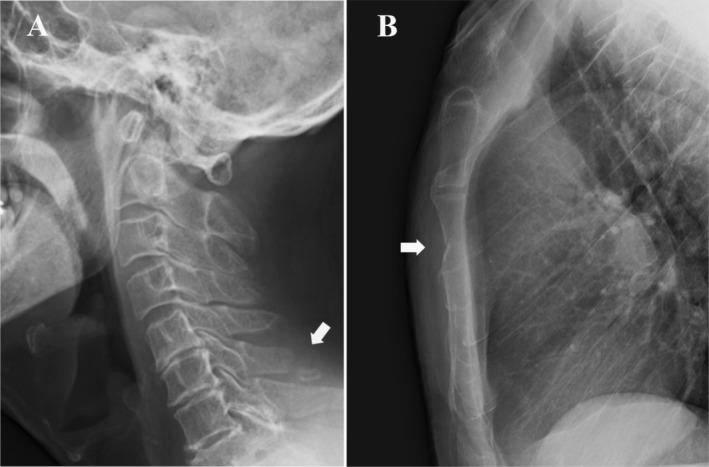

一例与颈椎骨折相关的胸骨骨折

Sternal injuries are caused by two mechanisms: direct and indirect forces on the sternum. An indirect sternum fracture is usually caused by a forcible anteflexion of the spine. When a patient with back bruising complains of anterior chest pain, a sternal fracture should be considered in the differential diagnosis.

胸骨损伤由两种机制引起

胸骨上的直接和间接作用力。间接性胸骨骨折通常由脊柱的强力前屈所致。当伴有背部瘀伤的患者主诉前胸疼痛时,鉴别诊断应考虑胸骨骨折。